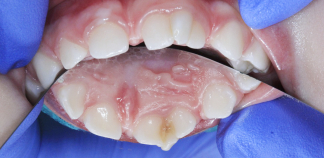

До лечения

Пришли с жалобой на кариес.

Пациенту 2 года.

Как лечили

Пролечен кариес трех сросшихся зубов под наркозом.

Лечение проведено за один визит.